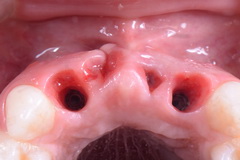

オペより2か月。美しい歯肉が再生しています。

28インプラントで多数歯欠損を治療した症例

※診療結果には個人差があります。

患者:65歳女性

主訴:

歯を綺麗にしたい。

費用:約200万円

メリット:インプラントなので入れ歯のように取り外す必要がない。硬いものでも食べることができる。

デメリット:手術が必要である。

備考:始めは義歯を装着されていましたが取り外して洗浄するのが辛いとのことでインプラント治療を行いました。

治療前

治療内容

治療後

5年経過時 問題なく経過しております